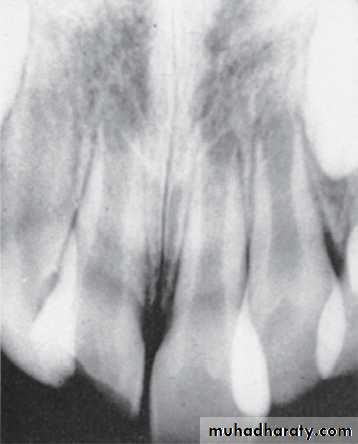

Closed apex maxillary central incisors (mature)Open apex maxillary central incisors (immature)

Patient’ age nearly 9 because the lower canines erupted and their eruption on 9-10 year and the upper lateral emerging now

This child is 7-8 years old because he has the upper maxillar centrals erupted (depending on schedule of time of eruption of permanent teeth (eruption lecture)